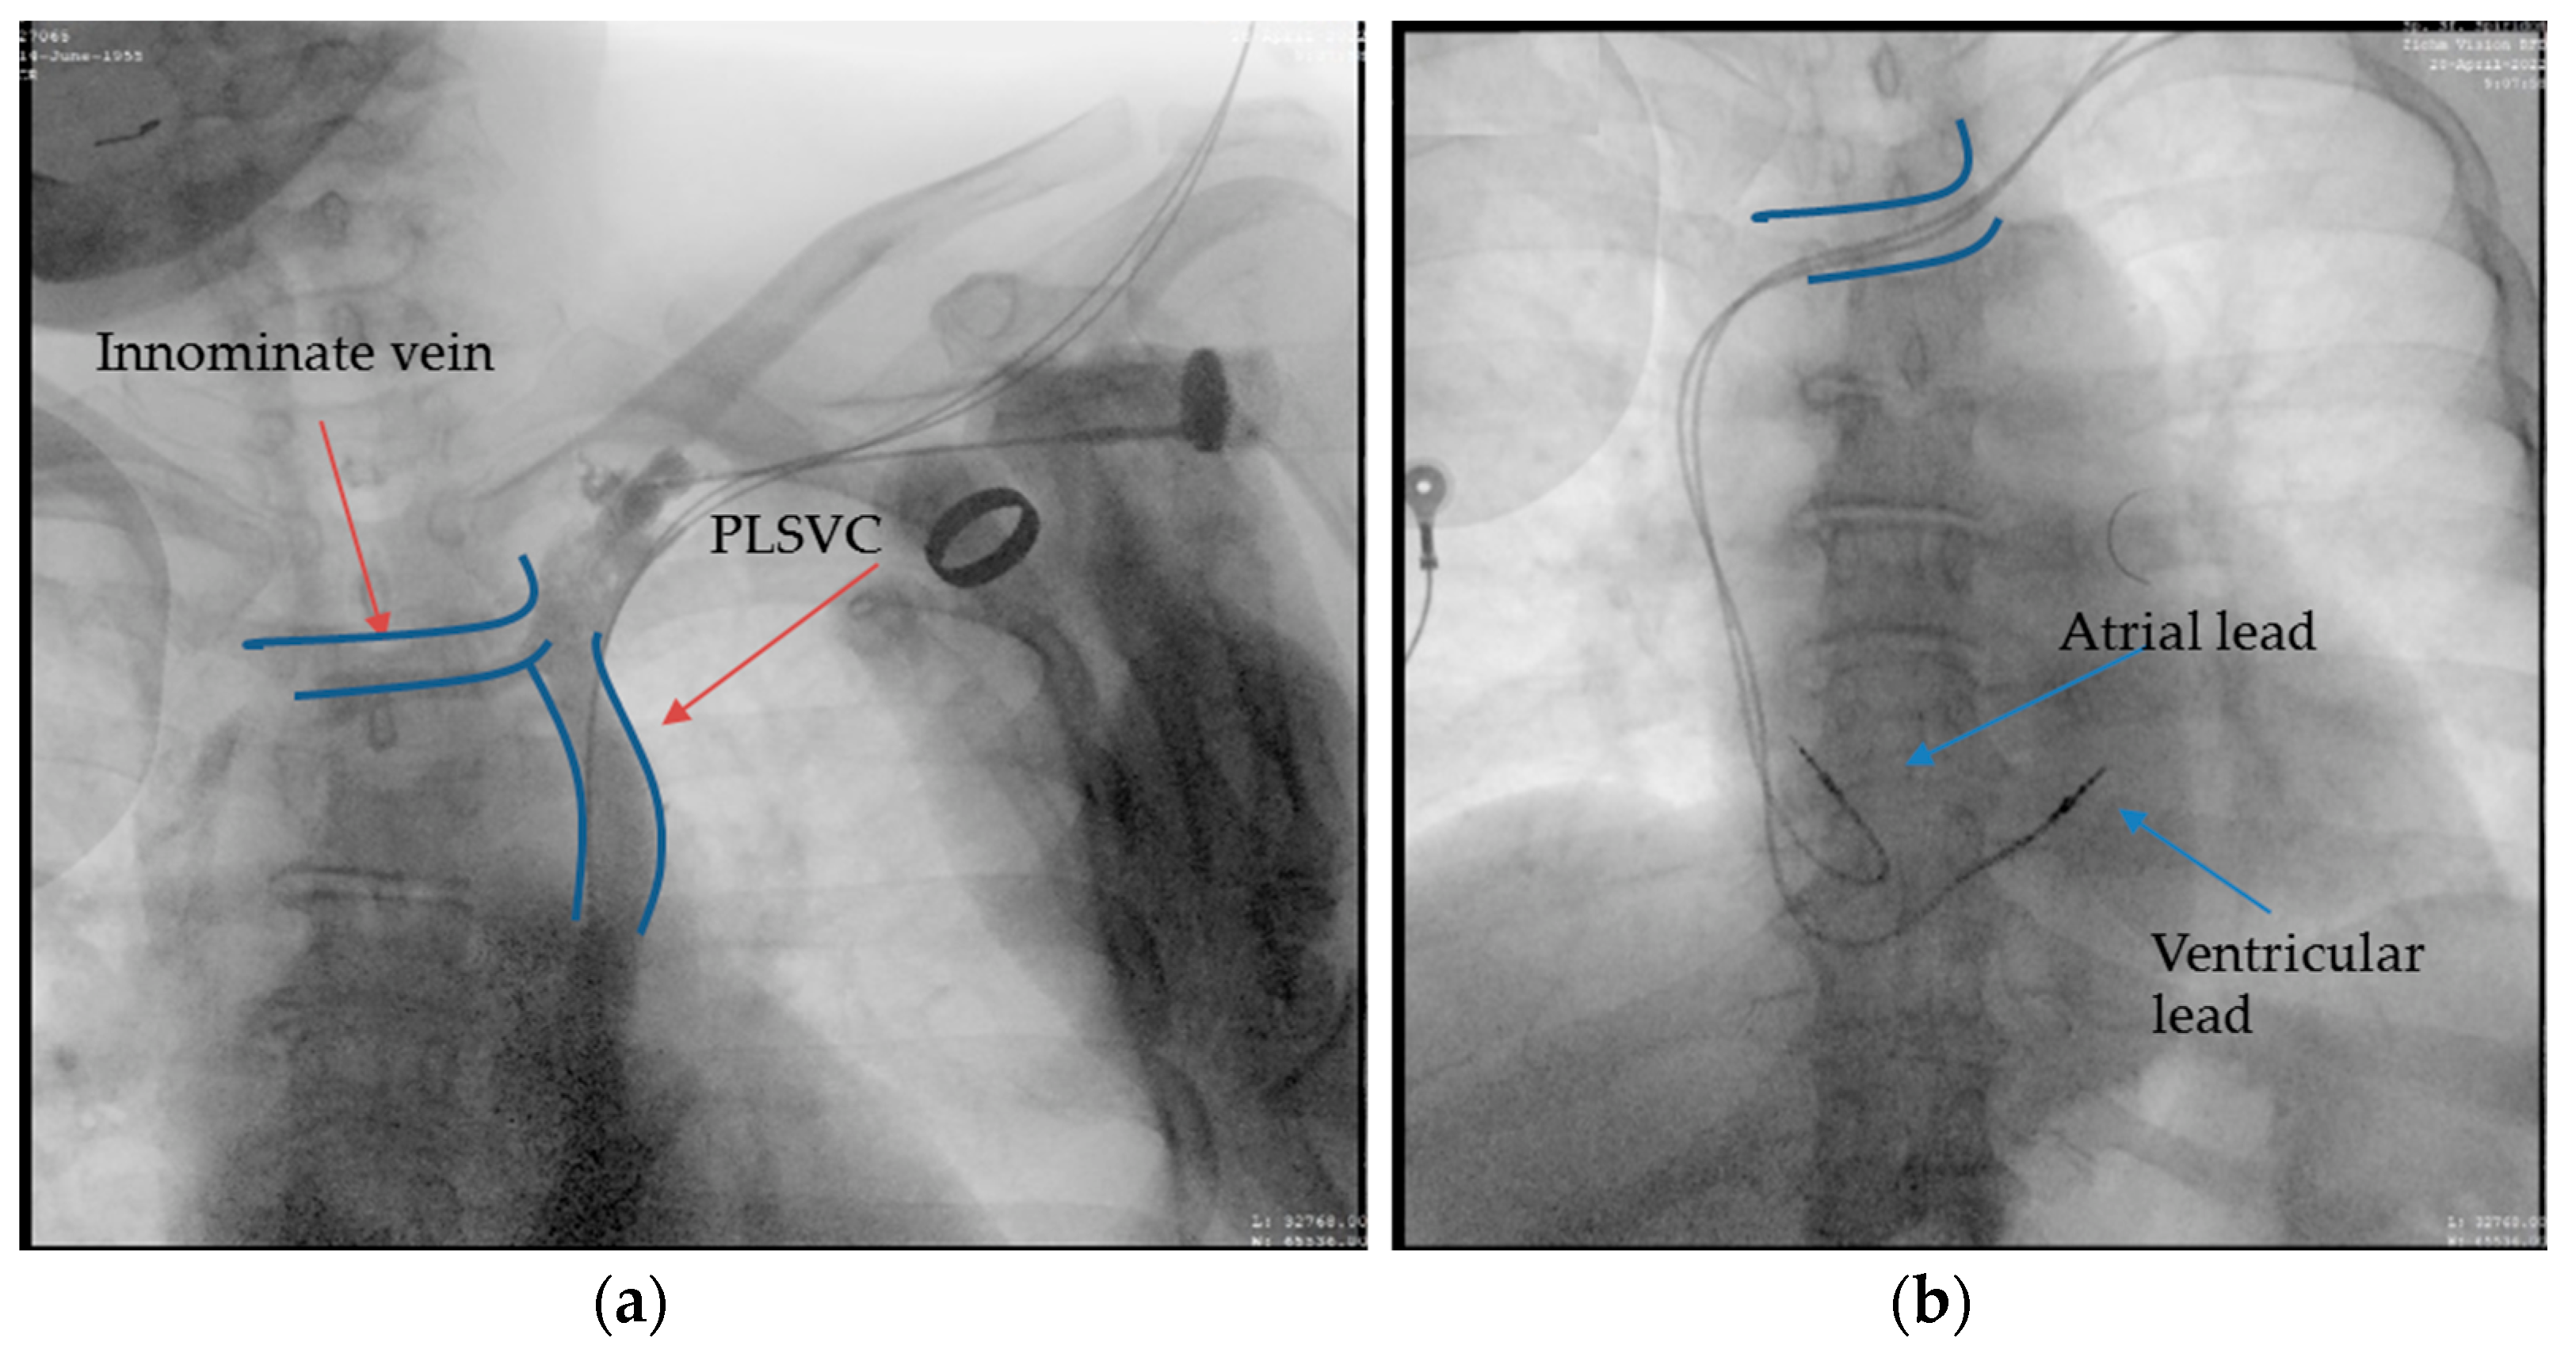

2.2. Case 2. (Type IIIa)